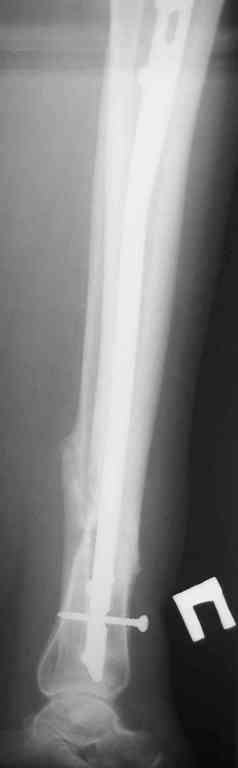

Прилагаются.

Да , обсуждалась и оптимальным штифтом был выбран " Мастер" Остеомед 10 мм и винты 5 мм, но увы все наши благие намерения разбились о нашу действительность и материальные возможности больной, обращение ее в страховую компанию и т.д., вообщем выкручивались из внутренних резервов, а они были такими 9 мм штифт Остеомед, под 4 мм винты. Ограничили нагрузку. Ошиблись еще и с оценкой сращения, дали полную нагрузку+ больная поправилась на 18 кг, и вот теперь имеем , что имеем.

Действитльность и возвожности остались прежнее, во внутренних резервах есть 11 мм стержень универсальный ( реконструктивный) "Деост-CHM" много спиц и аппарат + ось конечности и отломок штифта и надежда на Ваши советы.